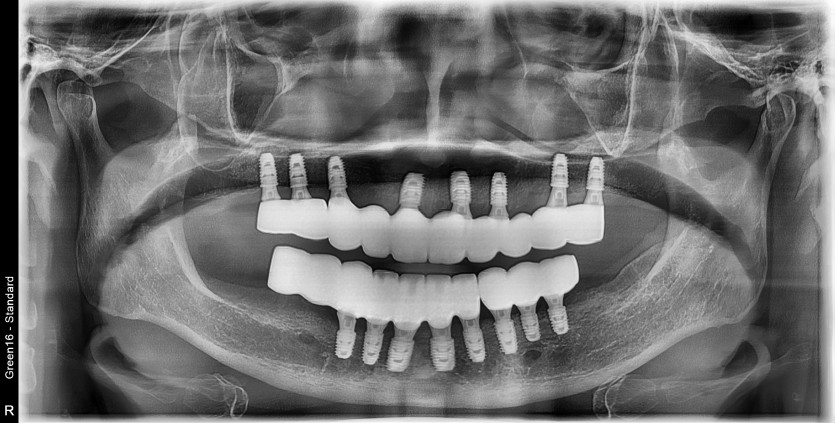

만 65세 상,하악 전체 임플란트 증례

상,하악 전체 임플란트 증례입니다.

16개의 임플란트로 완성하였습니다.